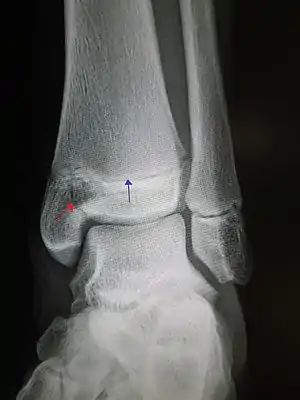

| Pott's fracture[5] | Percival Pott | bimalleolar fracture of the ankle | eversion of ankle | Pott's fracture at Who Named It? | |